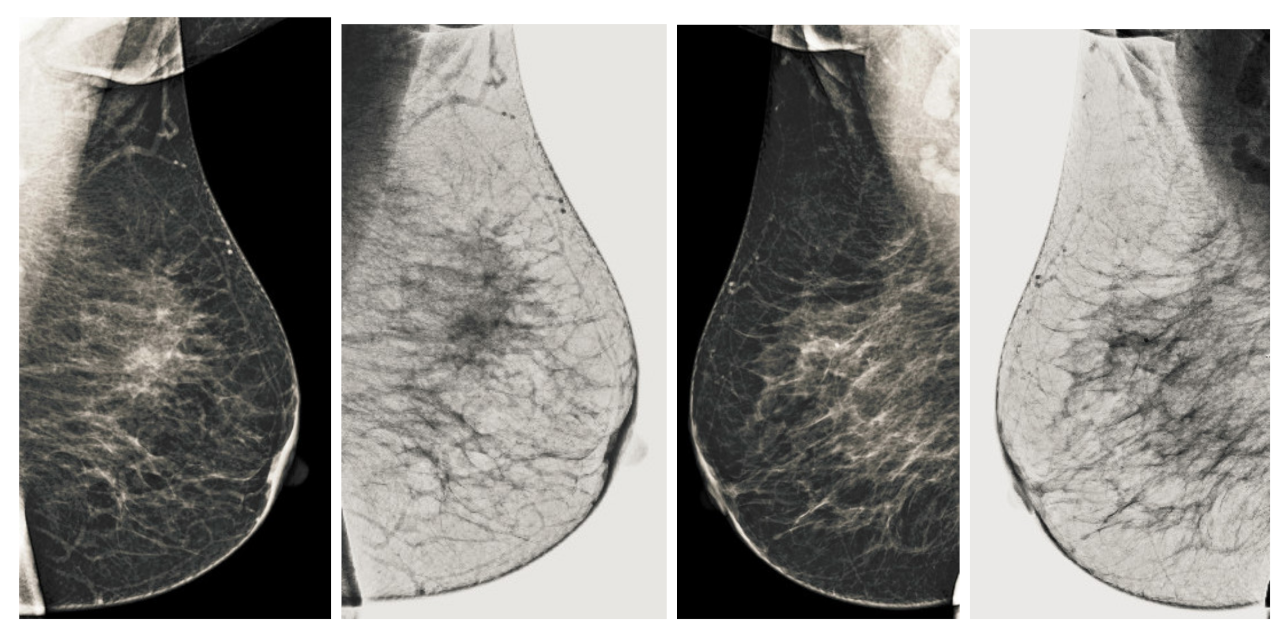

We process all three channels of mammography images. From our first step of the analysis, the green channel gives better contrast and more detail on the pectoral muscle than the other two channels. It has better histogram images that show good contrast distribution. However, there is still noise and uneven illumination due to the image acquisition process. Still, we cannot eliminate the analysis of the other two channels because we convert the three channels into a single grayscale image using the principal component analysis. It is the next step after removing uneven illumination and noise problem. We dealt with uneven illumination and noise using morphological techniques. We used basic morphological tactics called bottom hat and top hat operations to remove background noise and make the image contrast uniform. It is observed that there are variations of intensities in the image, and especially the region of the pectoral muscles, as shown in Figure 4. Because the intensity level of the pectoral muscle varies significantly due to an abnormal region or cancerous region, and these are significantly lower than the background intensity. Scanning the cancerous area is critical because of tiny nerves or vessels. The morphological bottom hat improves image analysis of such a region and provides more information to the image while lowering the noise level and observing the cancerous region. The Equation (1) shows the mathematical form of the bottom-hat operation.

Figure 4.

Overall conversion process PCA based color-to-gray conversion. Resulting well contrast mammogram image is obtained by using this PCA technique.

The • shows the close operation. Then, we applied the top hat operation to increase the contrast and control the change in contrast of the pectoral muscle or the cancerous region. The mathematical representation of the top hat operation is defined in the Equation (2). The ∘ shows the opening operation. An improved image is obtained with uneven illumination and noise suppression, but an appropriate grayscale image is still required. We used principal component analysis in the following steps to obtain a well-contrasted mammography image.

3.3. Conversion into Grayscale Well Contrasted Image

After the background uniformity of the channels and eliminating most of the non-uniform regions of the image, the next most important task is to combine all the channels into a single grayscale image. It is necessary to remove the amount of data to be processed by the later stages of breast cancer detection. Many types of research have selected the green channel, instead of selecting the green channel only for its possible grayscale representation as adopted by many earlier researchers in this area [44], we prefer to use all three channels with the help of principal component analysis (PCA) to obtain a grayscale image.

Color-to-gray conversion is adopted to combine all previously processed tricolor images with their respective non-uniform removal process. We used the PCA technique for converting three channels to a grayscale image. The first step involves forming a vector color image () by stacking three channels side by side. Then, a image () is calculated from its original image to separate the luminance and chrominance channels using the conventional transfer function as defined in [45]. In the next step, the eigenvalues and their corresponding eigenvectors are projected by adopting the method of principal component analysis (PCA). The final gray image is calculated by a weighted linear combination of three projections, where the weights are calculated as a percentage of their eigenvalues. The final output is scaled to as shown in the Figure 4. Next, we use the first subspace projection, which dominates the color-gray mapping results due to its substantially larger eigenvalue. However, the second and third subspace projections contribute a small proportion to the detail of the original three-channel image in the resulting grayscale image, as shown in Figure 4.